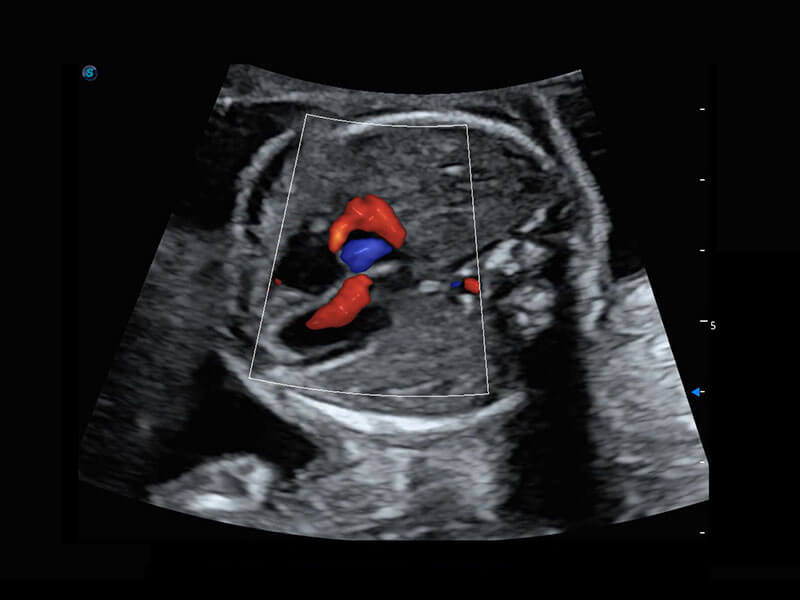

早孕筛查

P60在胎儿早孕期超声筛查中为您带来优异的图像质量。

• 胎儿体循环